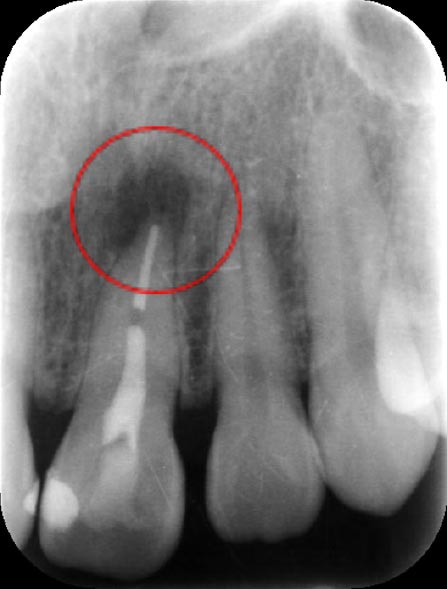

治療前

1ヶ月後

5ヶ月後

例として上記根管治療のレントゲン写真による変化を見ると、治療前にあった根尖病変は治療の経過と共に治癒してきていることがわかります。治療直後では大きな変化は生じません。